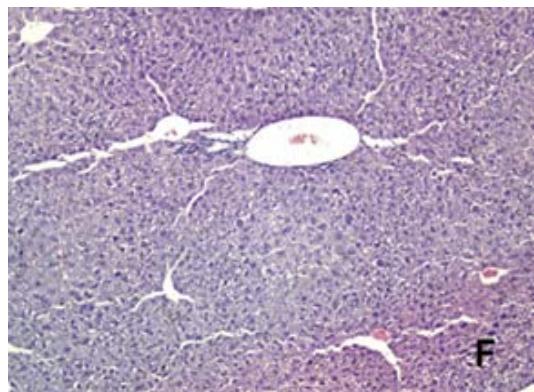

0 G6 e G7 não apresentaram desenvolvimento de necrose, mostrando morfologia hepática normal similar ao G1, conforme a Tabela 1 e Figuras 4A, 4F e 4G.

Escore 0 (sem necrose); escore 1 (necrose $< 10\%$ do fígado); escore 2 (necrose entre $10 \mathrm { - } 25\%$ do fígado); escore 3 (necrose entre $25 \mathrm { - } 50\%$ do fígado); escore 4 (necrose $> 50\%$ do fígado). Esses resultados podem ser visualizados na Figura 4, que inclui fotomicrografias representativas e a porcentagem de área de necrose hepática.

FAnálisehistopatológicao tecido hepáticocamundogos Swiss intoxicados codosúicaacetaminof iotatagtiai çõot ivtoopticaqãt quantoFieesentauotivamenteagns fora corada hematoxilina e eosina (HE) e capturadas com um aumento de $100 \times$.

O EBUM quandoadministrado nas concentrações de 100 mg/Kg ou 500 mg/Kg (G6 e G7) mostram-se seguros visto não ter alterado os níveis séricos das enzimas hepáticas AST, ALT e BT, além de ter melhores desempenhos frente à parâmetros analisados de estresse oxidativo, evidenciado pela determinação da GSH (Figura 3B). A morfologia das células hepáticas também não foi alterada, conforme demonstrado nas Figuras 4F e 4G.